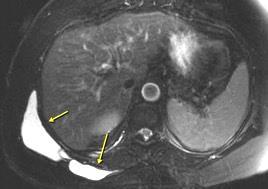

Tumor desmoide (“Fibromatosis agresiva”)

T1: Isointensos con músculos.

T2: Señal intermedia y de alta intensidad.

Presencia frecuente de áreas curvilíneas y lineales dentro de la lesión

Mansour J et al. Diagnostic and Imaging Approaches to Chest Wall Lesions. Radiographics 2022